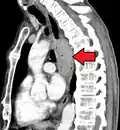

Additional testing is needed to assess how much the cancer has spread (see § Staging, below). Computed tomography (CT) of the chest, abdomen and pelvis can evaluate whether the cancer has spread to adjacent tissues or distant organs (especially liver and lymph nodes). The sensitivity of a CT scan is limited by its ability to detect masses (e.g. enlarged lymph nodes or involved organs) generally larger than 1 cm.[44][45] Positron emission tomography is also used to estimate the extent of the disease and is regarded as more precise than CT alone.[46] PET/MR as a novel modality has shown promising results in preoperative staging with fair feasibility and good correlation in comparison to PET/CT. It can enhance tissue differentiation with lowering the radiation dose to the patient.[47] Esophageal endoscopic ultrasound can provide staging information regarding the level of tumor invasion, and possible spread to regional lymph nodes.

Contrast CT scan showing an esophageal tumor (coronal view)